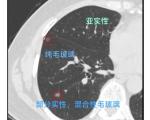

磨玻璃结节和实性结节的区别是什么?

肺磨玻璃结节、实性结节危险性比较

肺磨玻璃结节、实性结节哪种更危险?